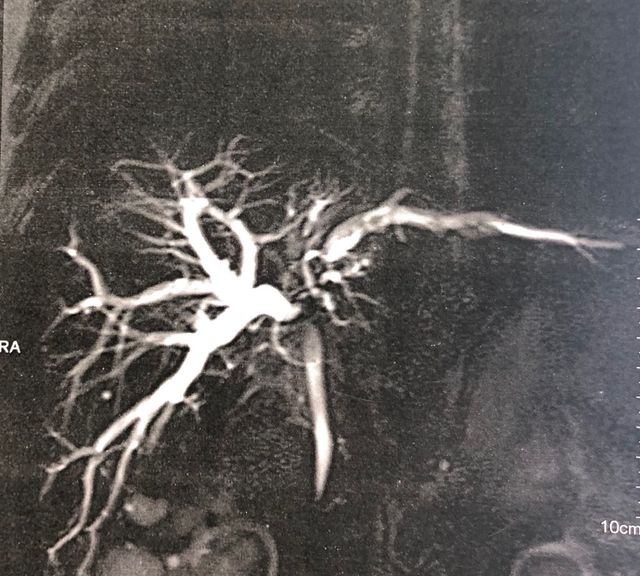

Recurrent pyogenic cholangitis (RPC) - 67 yr old Bangladeshi lady presented with recurrent episodes of jaundice, fever and pain for past 1 year

Interesting images: Recurrent pyogenic cholangitis (RPC) 67 yr old Bangladeshi lady presented with recurrent episodes of jaundice fever and pain for past 1 year. MRCP and CT scan showed left duct stricture with left sided IHBRD and CBD stones and atrophy of left lateral segment. As she 4 duct was also involved we did a left hepatectomy with hepaticoduodenostomy . Reccurant pyogenic cholangitis is a disease charecterised by multiple instances of biliary bacterial infection, hepatic abcesses , multiple stricturing of bile ducts with pigment stone formation in the intrahepatic and extrahepatic biliary tree. This can cause reccurant episodes of cholangitis, chronic illness ultimately leading to liver failure. It is more common in the far east population. Management includes long term biiary drainage with liver resections for segmental disease and liver transplantation in patients with end stage liver failure . The last CT scan shows another CT scan another similar patient with huge intrahepatic stones and abscesses managed successfully by surgery and long term PTBD.